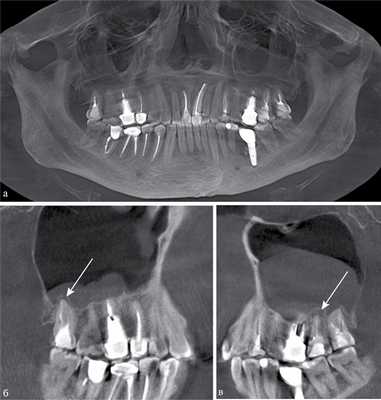

По результатам нашего исследования у 24 (14,5%) пациентов были обнаружены признаки хронического периодонтита в области премоляров и моляров верхней челюсти (рис. 1). Глубокий кариес был диагностирован у 4 (2,4%) пациентов, кисты верхней челюсти в области корней премоляров и моляров визуализировались в 6 (3,6%) случаях.

Рис. 1. КЛКТ. Панорамная (а) и мультипланарные реконструкции правого (б) и левого (в) верхнечелюстных синусов пациента М., 37 лет. Диагноз: двусторонний одонтогенный хронический верхнечелюсной синусит. Отмечаются КТ-признаки хронического гранулематозного периодонтита зубов 1.8, 2.7, 2.8 (в виде очагов деструкции у верхушек корней, округлой формы, с четкими ровными контурами). Нижние костные стенки синусов истончены, не прослеживаются в области периодонта зубов 1.8 и 2.8 (указаны стрелками). В нижнем отделе правого верхнечелюстного синуса определяется пристеночное мягкотканное образование гомогенной структуры с полицикличным верхним контуром. Левый верхнечелюстной синус субтотально заполнен мягкотканным содержимым гомогенной структуры с округлым верхним контуром.